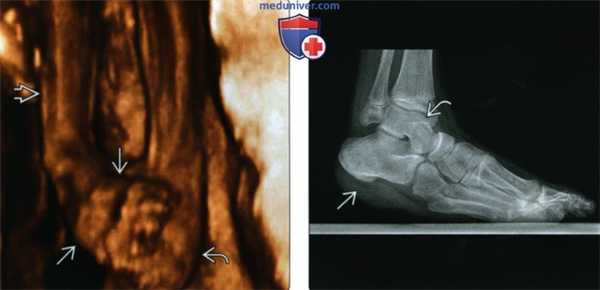

(Слева) При УЗИ плода на 3D-реконструкции определяется двухсторонняя косолапость: передний отдел стопы в положении приведения располагается в одной плоскош с костями голени. Стопа другой конечнош приведена и находится в положении подошвенного сгибания.

(Справа) Рентгенография в боковой проекции: определяется неполная коррекция косолапости вследствие сохранения эквинусного положения пяточной кости. Такой вид деформации получил название «стопа-качалка». Обратите внимание, что купол таранной кости выглядит уплощенным. Также наблюдается остаточная варусная деформация заднего и переднего отделов стопы.

(Слева) 3D УЗИ плода в 24 нед. Односторонняя изолированная косолапость. Определяется косолапость справа, левая стопа не изменена. Трехмерные изображения позволяют лучше оценить выраженность изменений.

(Справа) Режим трехмерного отображения костных структур. Большеберцо-вая, малоберцовая и плюсневые кости. Для исключения синдрома амниотических перетяжек или эктро-дактилии необходимо сосчитать плюсневые кости и пальцы стопы. У плода в 23 нед. с изолированной косолапостью определяются пять плюсневых костей. (Слева) На момент скринингового УЗИ анатомии плода в 20 нед. и 4 дня отмечается двусторонняя косолапость. Во фронтальной плоскости отчетливо определяется, что стопы повернуты к срединной линии и навстречу друг другу. Другие аномалии не обнаружены.